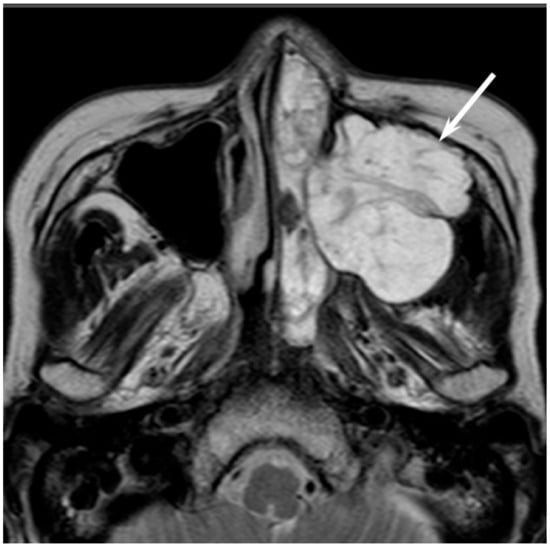

Low-grade sinonasal ACCs may present as polypoid lesions that remodel the bone and mimic a simple polyp, whereas high-grade sinonasal ACCs may present as large irregular masses with bone destruction and heterogeneous density or signal intensity [18]. The growth pattern of maxillary sinus ACCs can be classified into expansile type with minimal bony defects and destructive type with extensive bony defects, and these tumors usually extend to the nasal cavity and, occasionally, to the retroantral fat pad, pterygopalatine fossa, or orbit [19]. ACCs show isointensity on T1WI and iso- to hyperintensity on T2WI, depending on the amount of cellularity (Figure 3). ACCs exhibit the greatest propensity for perineural spread, and the maxillary division of the trigeminal nerve is most commonly affected by sinonasal ACCs. These tumors sometimes easily extend into intracranial components including the cavernous sinus and the Gasserian ganglion, which are far away from the original site [20,21]. Furthermore, for the surgeons, it is often important to first evaluate on images whether the tumor is resectable or not and far away from vital structures. In cases with an advanced tumor, fluid collection and thickened mucosa caused by the isolated sinuses sometimes make it difficult to diagnose and stage the disease.

Figure 3. Adenoid cystic carcinoma of the left maxillary sinus and nasal cavity. T2-weighted image showing a well-demarcated, lobulated, heterogeneously and strongly hyperintense lesion (arrow).